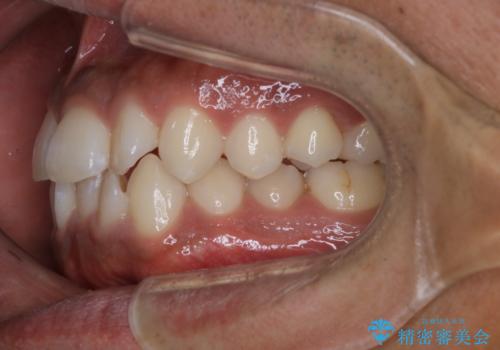

- 上下の前歯のがたつきが気になるとご相談にいらした方です。光加速矯正装置(オルソパルス)を用いて短期間で仕上げることが出来ました。

一般的に噛む力が強い方は矯正治療に時間がかかると言われてます。光加速矯正装置(オルソパルス)を用いることで短期間で仕上げることができました。